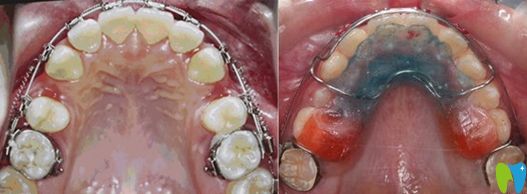

牙弓狹小需要擴弓的病例圖

擴弓矯正的前后效果對比圖